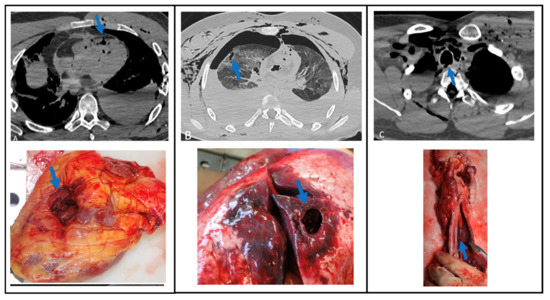

Figure 1, Figure 2 and Figure 3 show correlations between CT scan data and autopsy photographs.

Figure 2. Correlations between CT scan and autopsy concerning thoracic lesions (arrows) (A) heart lesion, (B) right lung lesion, (C) lesion of the posterior wall of the trachea.

Figure 3. Correlations between CT scan and autopsy concerning abdominal lesions (arrows), (A) right colon and right kidney lesions, (B) lesion of the head of the pancreas, (C) liver lesion.